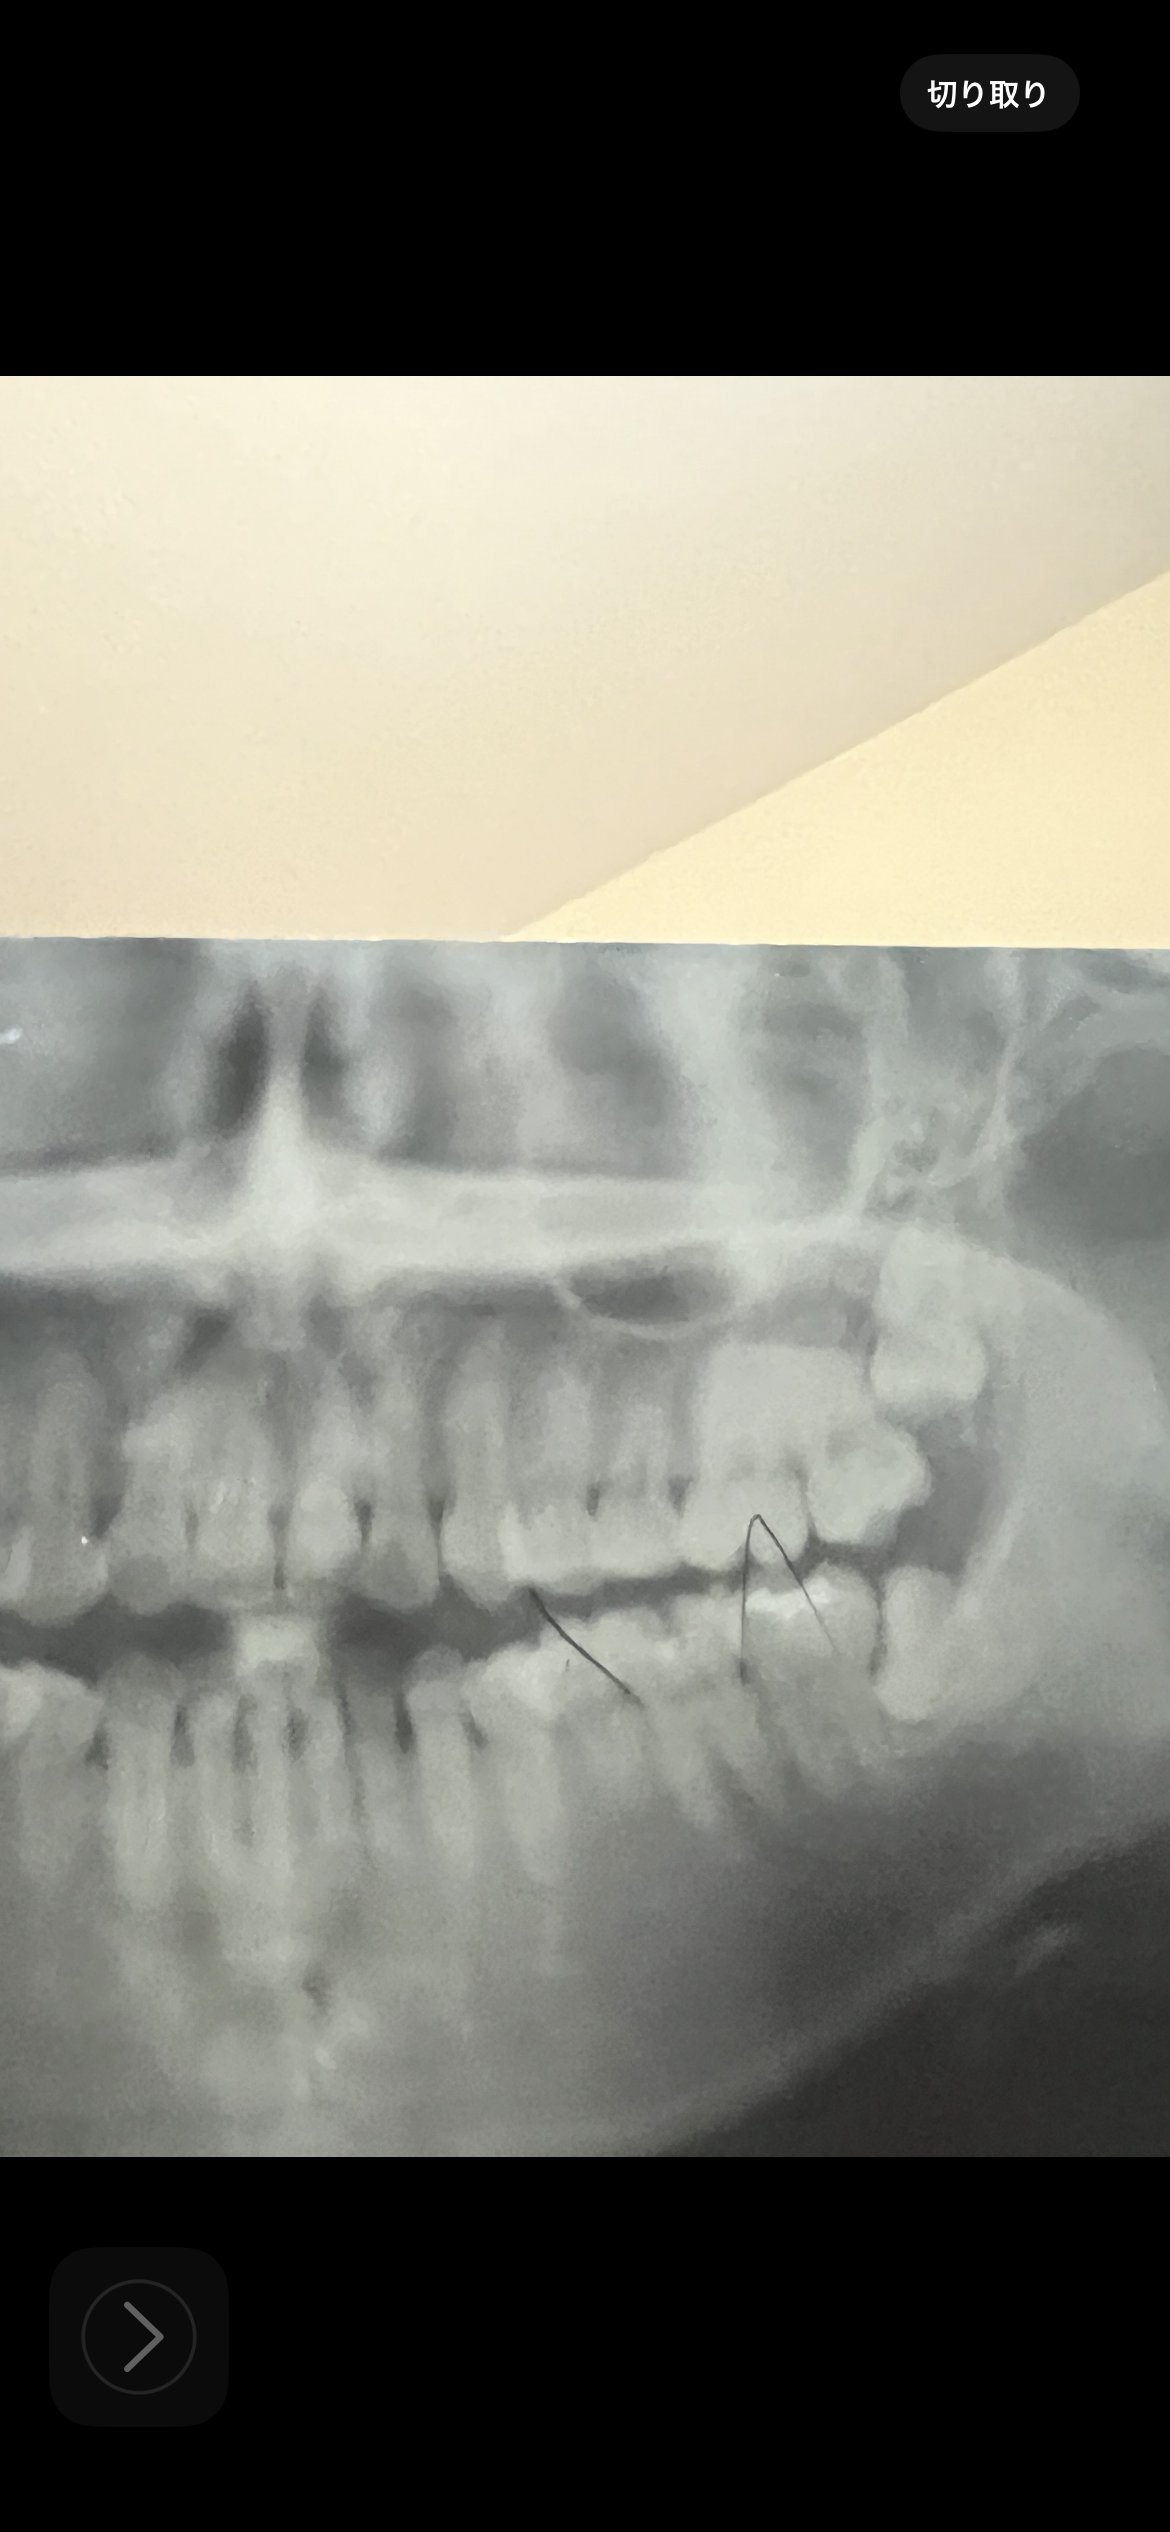

矯正終了時に頂いたレントゲンです。

埋伏智歯があります。

片側から後鼻漏や鼻詰まりがありますが、歯性上顎洞炎の可能性はありますか?

埋伏している親知らずがあるようですが、それと鼻の症状、頭痛との関連はあまりないように思います。